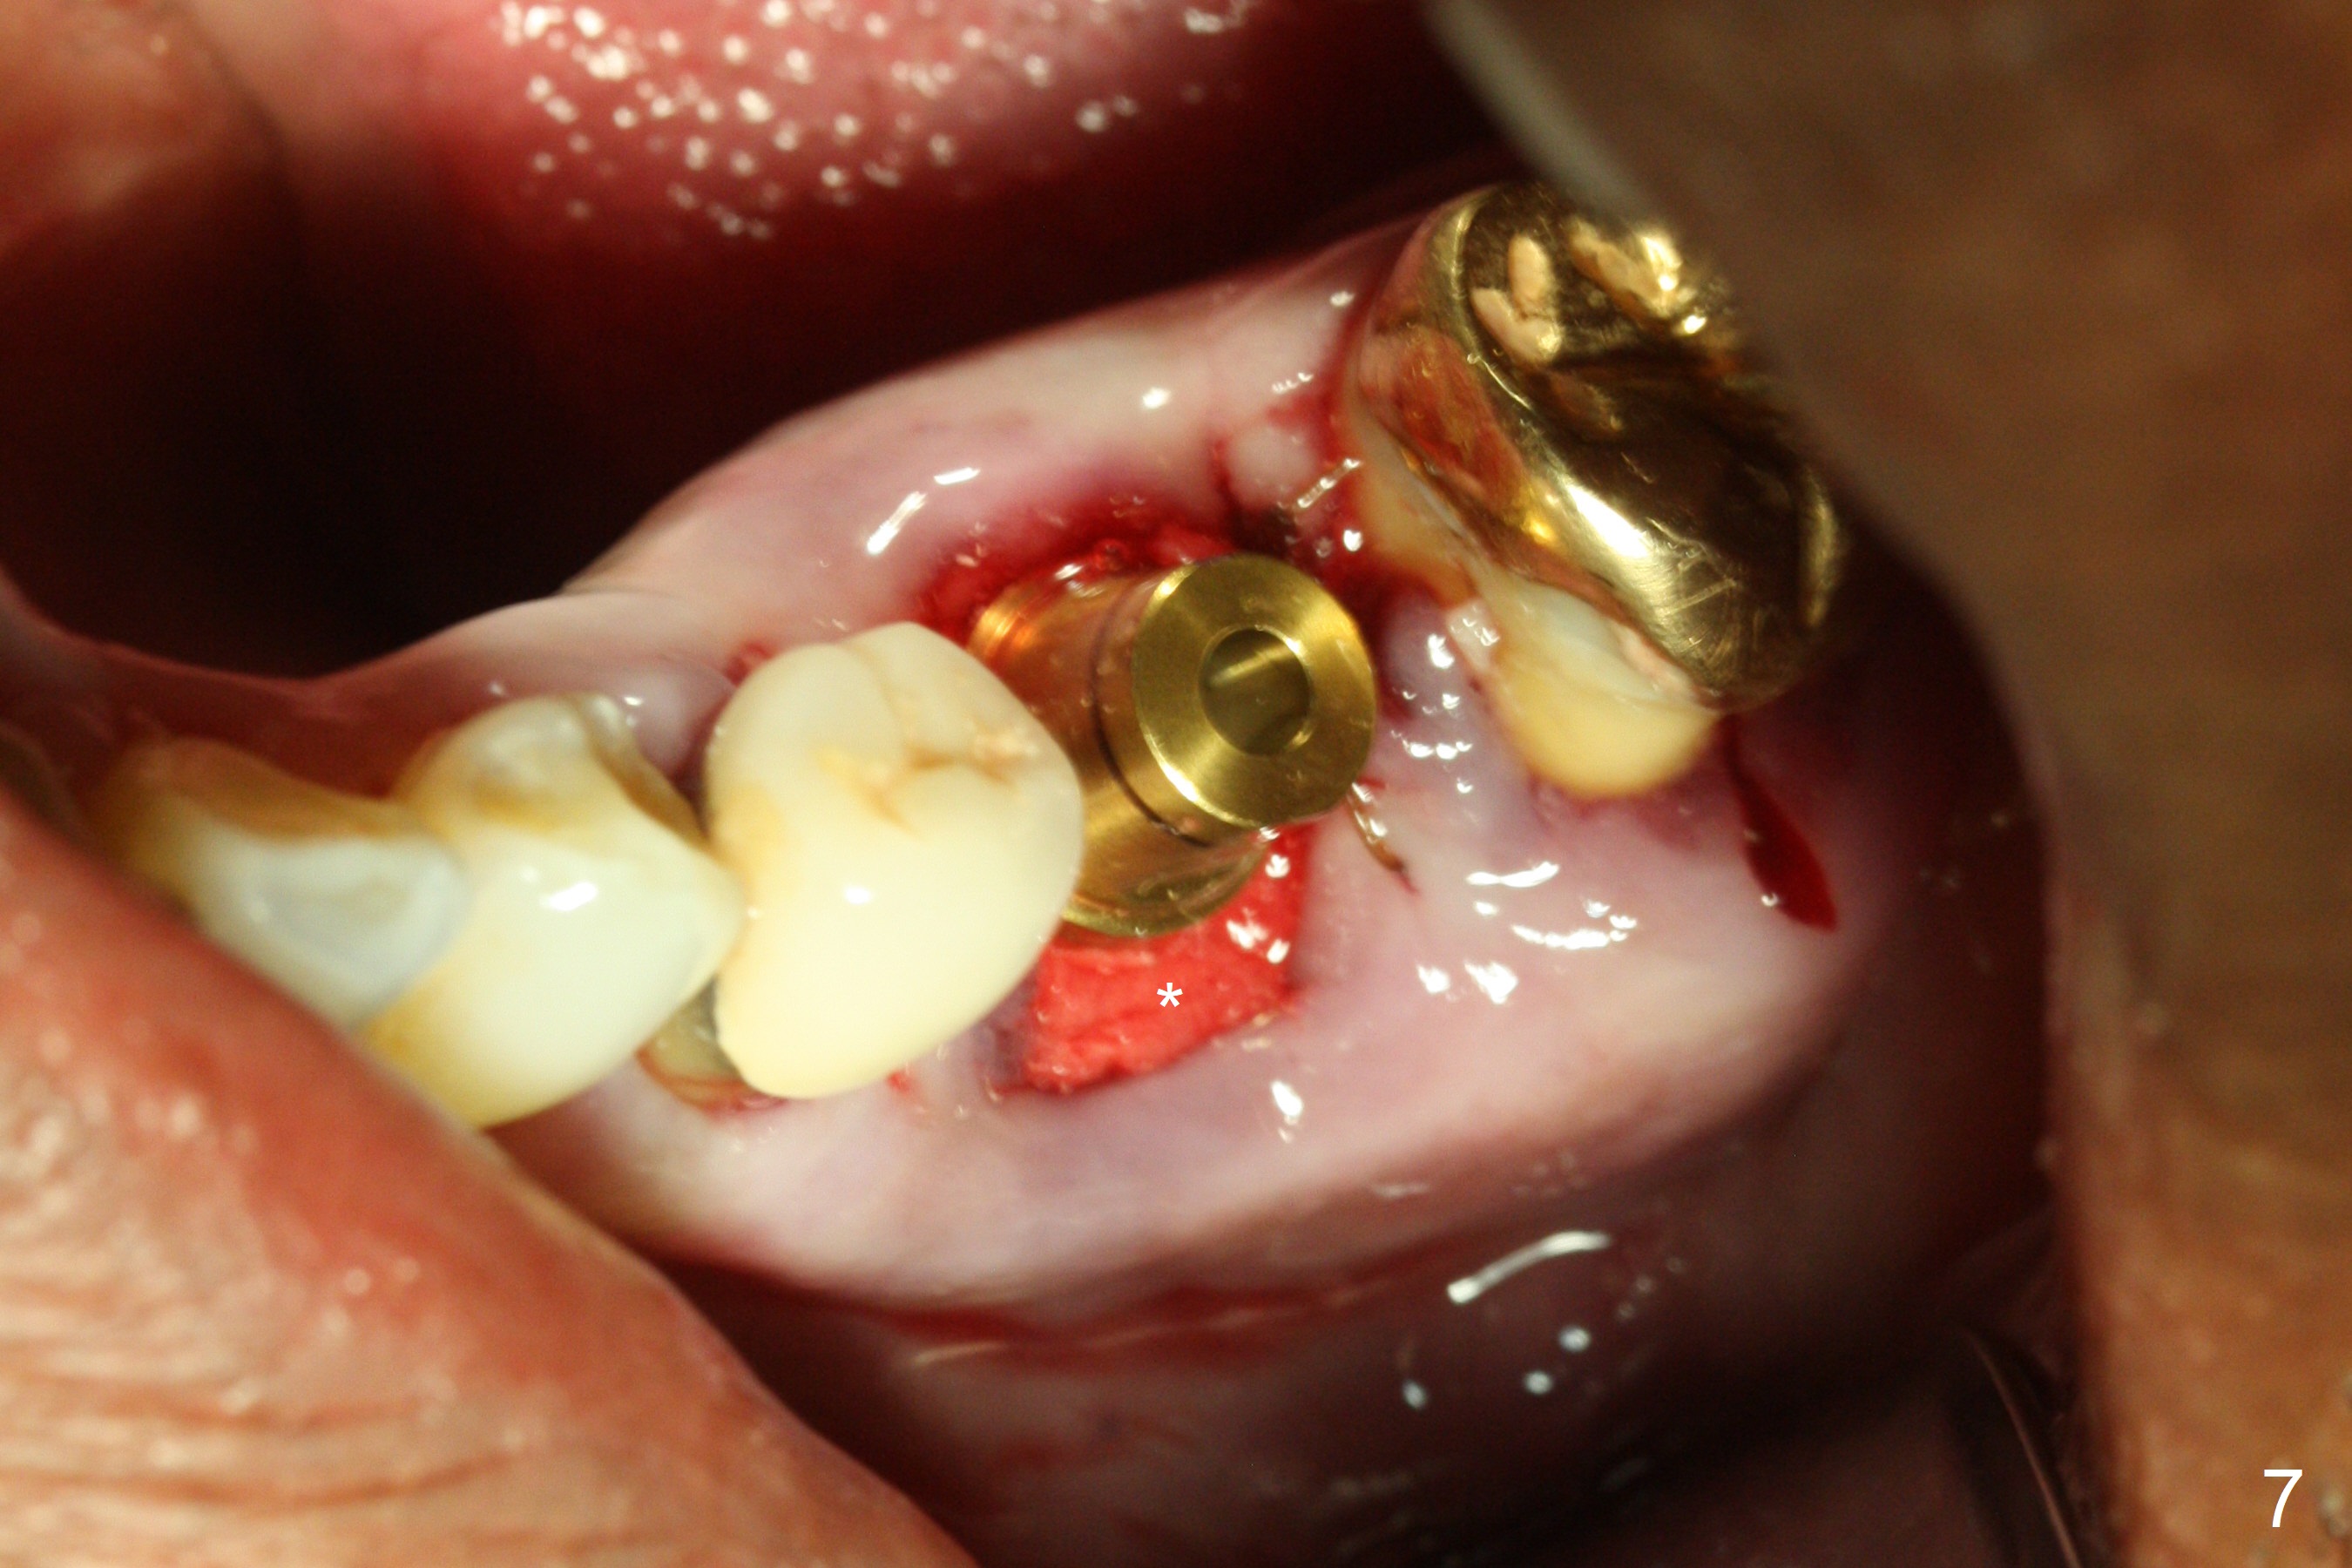

After extraction of the supraerupted tooth #19 with severe buccal gingival recession, the buccal and lingual plate are found to be lost. The sockets are fused and flat without the septum. The bone is hard and painful for the initial osteotomy with infiltration anesthesia (Fig.2). Following block anesthesia, the initial osteotomy depth extends to 8 mm (Fig.3,4). With apparent 4.9 mm clearance, the osteotomy is further extended to 10 mm. The osteotomy walls are apparently intact without severe hemorrhage after each drill. Due to the thick gingiva and severe bone loss, a 5x12 mm implant is intentionally placed 3 mm above the base of the socket bone (Fig.5,6 (yellow dashed line)). Vanilla Cortical and Cancellous allograft (Fig.6 *) is placed around the exposed implant and 7.8x5(6) mm abutment with 4 and 2 mm buccal and lingual gaps. Next collagen plug cut in strip is placed to fill the most coronal aspect of the socket (Fig.7 *). The buccal and lingual gingivae are approximated with sutures proximally. Finally periodontal dressing is applied. Since the Inferior Alveolar Canal is vague in intraop PAs (Fig.4,5), there is worry about potential nerve damage during and after osteotomy. This should be no issue if preop panoramic X-ray is reviewed with measurement (Fig.8). The bone graft appears to remain in place nearly 4 months postop (Fig.9). Two weeks later, he returns for impression. When the provisional is removed, the gingiva is unhealthy. Without the provisional and with improved oral hygiene, the gingiva is healthy one week later, but the tooth #18 is symptomatic. The latter is extracted with socket preservation (Fig.10 *). There is no apparent bone loss around the implant at #19 6.5 months post cementation (Fig.11).